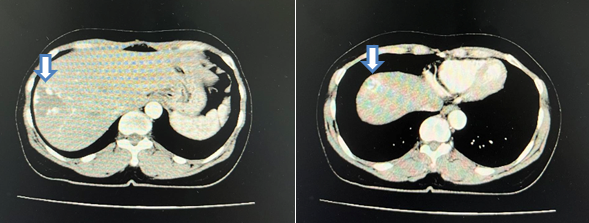

- Chụp cắt lớp vi tính ổ bụng:

Hình 1: Cắt lớp vi tính ổ bụng (09/06/22): Hình ảnh nhiều khối ngấm thuốc bàng quang (mũi tên) – Theo dõi u bàng quang đa ổ

Hình 2: Cắt lớp vi tính ổ bụng (09/06/22): Hình ảnh 2 khối u máu gan ở hạ phân thùy VII-VIII kích thước lần lượt là 35x38mm và 19x20mm (mũi tên)

- Cắt lớp vi tính ổ bụng:

Hình 6: Cắt lớp vi tính ổ bụng (16/06/23): không thấy các tổn thương thứ phát tại bàng quang (mũi tên)

Hình 7: Cắt lớp vi tính ổ bụng (16/06/23): Hình ảnh u máu gan phải, khối lớn nhất kích thước 35x38mm (không thay đổi đáng kể so với phim cũ 06/2022) (mũi tên)

Hình 8: Cắt lớp vi tính ổ bụng (06/03/24): Không thấy hình ảnh u cục, tổn thương thứ phát tại bàng quang (mũi tên)

Hình 9: Cắt lớp vi tính ổ bụng (06/03/24): Hình ảnh u máu gan phải, khối lớn nhất kich thước 36x52mm (mũi tên)